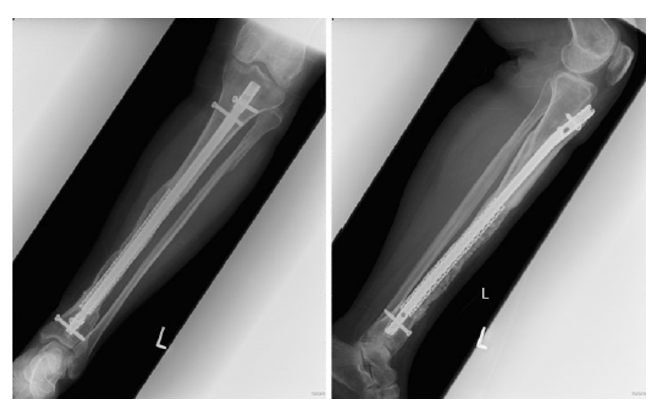

53y  M  车祸损伤左侧胫腓骨远端开放性粉碎性骨折Gustilo IIIB;AO 43-C3

Stage I清创、外支架固定

• 骨缺损6cm

• 软组织缺损

• 距骨关节面外露

带抗生素骨水泥旷置游离股薄肌瓣覆盖

术后复查外支架维持稳定Spacer位置理想力线良好

处理流程

• 细菌培养:金黄色葡萄球菌

• 敏感抗生素使用2个月(环丙沙星)

• 复查WBC 、CRP、ESR

• 8W后,炎症指标正常、创面修复,骨扫描检测(-)

• 外支架拆除改石膏固定

Stage II取出Spacer   混合材料植骨    仔细缝合软组织覆盖良好

髓内钉内固定踝关节融合